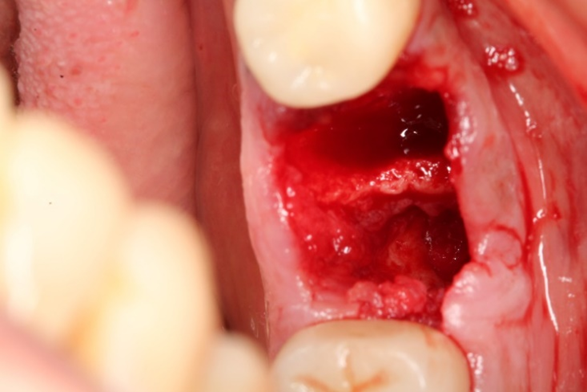

Uma paciente de 62 anos de idade apresentou-se com queixa de odor ruim na região do dente 46, pus, bolsa profunda e sangramento à sondagem. Os exames radiográficos evidenciaram lesão periapical, tratamento endodôntico e uma linha de fratura condenando a sobrevivência do elemento dentário 46. Assim, o elemento foi extraído e foi instalado um implante dentário de conexão interna morse no momento da exodontia. O mesmo foi estabilizado a 20Ncm e o parafuso de cobertura foi instalado. Em seguida, um biomaterial de origem bovina foi compactado no GAP e uma membrana não absorvível foi posicionada protegendo o biomaterial.

Após a análise clínica e tomográfica foi realizado o planejamento do caso: exodontia do dente 46 com a instalação imediata de um implante Cone Morse de corpo cônico (Maestro 4.0 X 9 – Implacil De Bortoli, São Paulo, Brasil), regeneração óssea guiada com biomaterial de origem bovina e colocação de uma barreira regenerativa não absorvível Cytoplast.